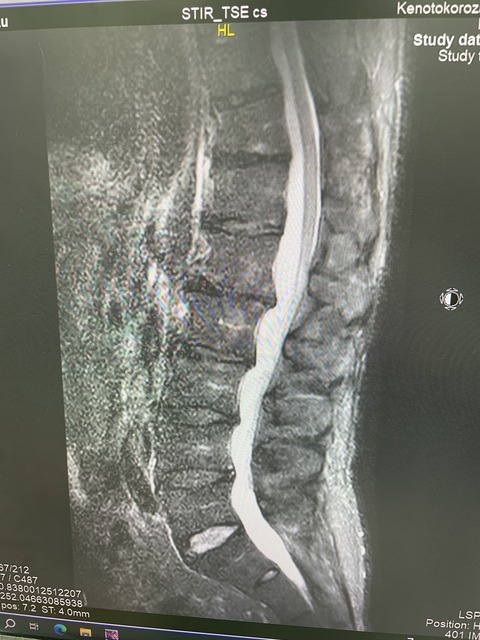

甲子園経験のある

大学野球選手が腰の痛みで来院

大学生まで、腰が痛くなった事はないと、

レントゲンを撮ると、強い分離症があり

痛みを乗り越えてきたのか、

無痛性の分離症だったのか、不思議です

現在は、分離症のサインあり、

分離症と診断し、トレーニングを開始しました

上を目指していきたいということで

強靭な腰を作りたいと思います